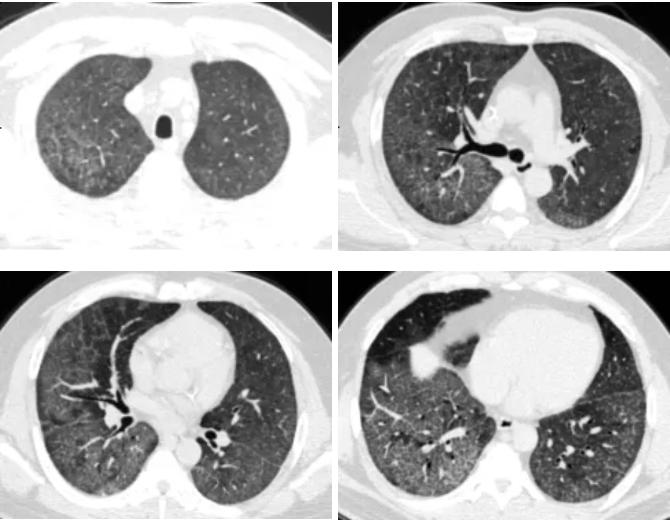

▲ 灌洗后胸部CT

术后患者生命体征稳定,已完全脱离氧气,日常生活无明显闷喘。